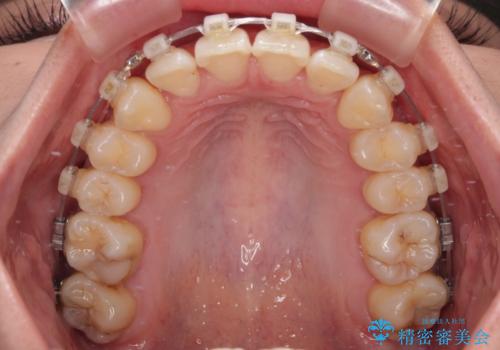

- クリアブラケット

- 1年6ヶ月

- 上顎前歯の突出感を気にして来院された患者様です。

舌の突出癖の影響で、歯列が前方に飛び出いた形態となっている状態でした。

抜歯矯正とするような歯列ではないため、舌のトレーニングを行いながら歯列を側方に拡大させることで口元の突出感を改善することとしました。